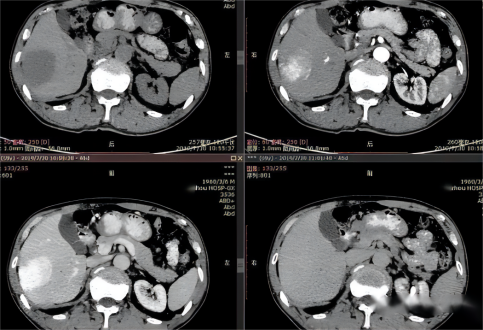

322页5题图片 |

原图 |

替换为此图